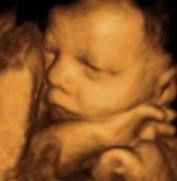

Gallery

Check out a few of the thousands of images we've enjoyed taking over the years.